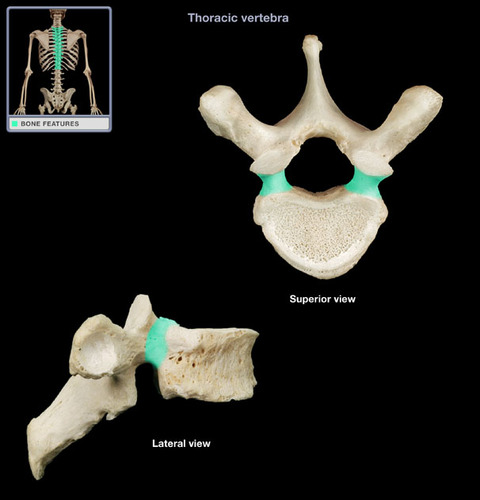

Thoracic Vertebrae

costal facets